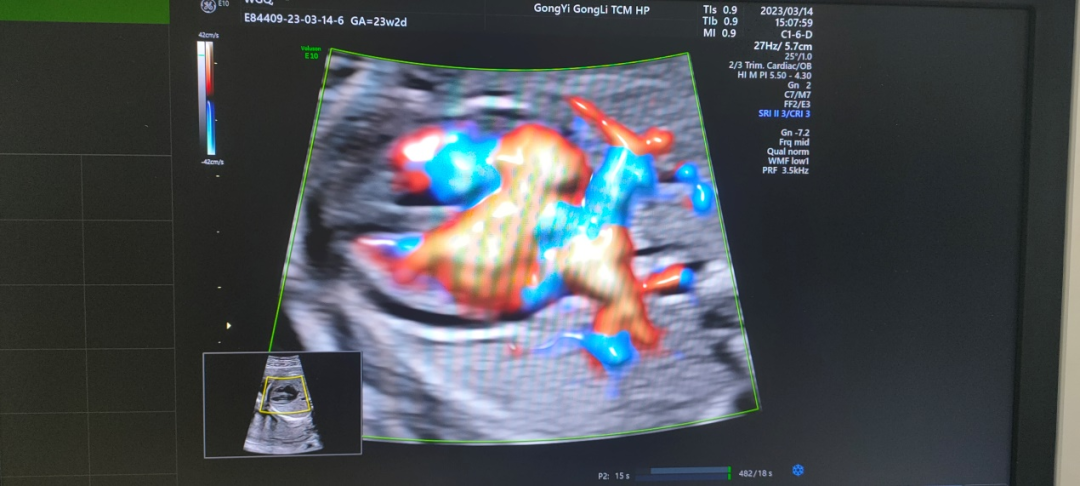

金标版GE-E10四维彩超是美国GE公司四维彩超的最新成员,专为尖端的妇女健康影像而设计,可广泛应用于妇产超声临床领域。尤其在产前超声筛查、孕早期成像、胎儿心脏成像、妇科泌尿和生殖医学等领域表现出色。

360°立体动态成像技术可清楚地显示子宫情况、输卵管形态、输卵管积水、通畅情况、伞端是否与周围组织粘连,大大提高输卵管的显示率和准确性;还能全方位立体动态地观察到胎儿生长发育状况。